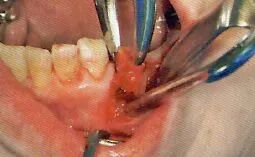

7 使用牙挺和拔牙钳拔牙

刮匙怎么使用拔牙中吸唾器的使用技巧_https://www.jmylbn.com_新闻资讯_第26张

使用牙挺和拔牙钳拔牙

为了使拔去的牙齿不要遗落到口腔内,吸唾器一定要放置到牙齿附近(图11)。牙齿拔去后,将重照灯照向拔牙窝。

吸唾器的使用目的

排除牙周膜腔的出血,将插入牙挺部位置于视野清晰处

残根和上颌智齿等大多只采用牙挺拔牙的方式拔牙。由于牙挺挤压损伤插入部位,会导致更多的出血,口腔卫生士可以以该部位为中心进行吸引。

刮匙怎么使用拔牙中吸唾器的使用技巧_https://www.jmylbn.com_新闻资讯_第27张

拔牙钳拔牙

*拔牙钳拔牙最基本的就是不用插入吸唾器。

将吸唾器置于将要拔去的牙齿的旁边,以防其掉落到口腔内部。

残根等掉落到口腔底侧时。主治医生需要准备小钳子等用具,为防出现误食,口腔卫生士还需要把持着吸唾器。

为了排除牙龈沟部的出血,拔牙钳把手周围要保持视野清晰(指的只是拔牙钳的把手在口腔外的部分)

基本上吸唾器都会将吸唾器从口腔内部取出。不过,若是没有办法尽快完成脱臼的话,一旦将拔牙钳从口腔内部取出,虽然下一次使用拔牙钳时会变得容易一些,但是仍需要使用吸唾器吸引牙龈沟部的出血。